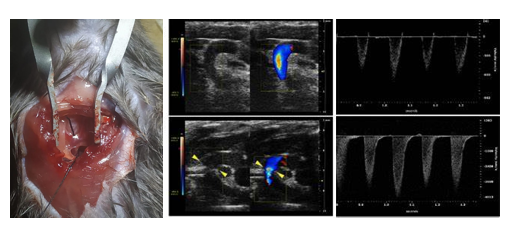

案例展示: